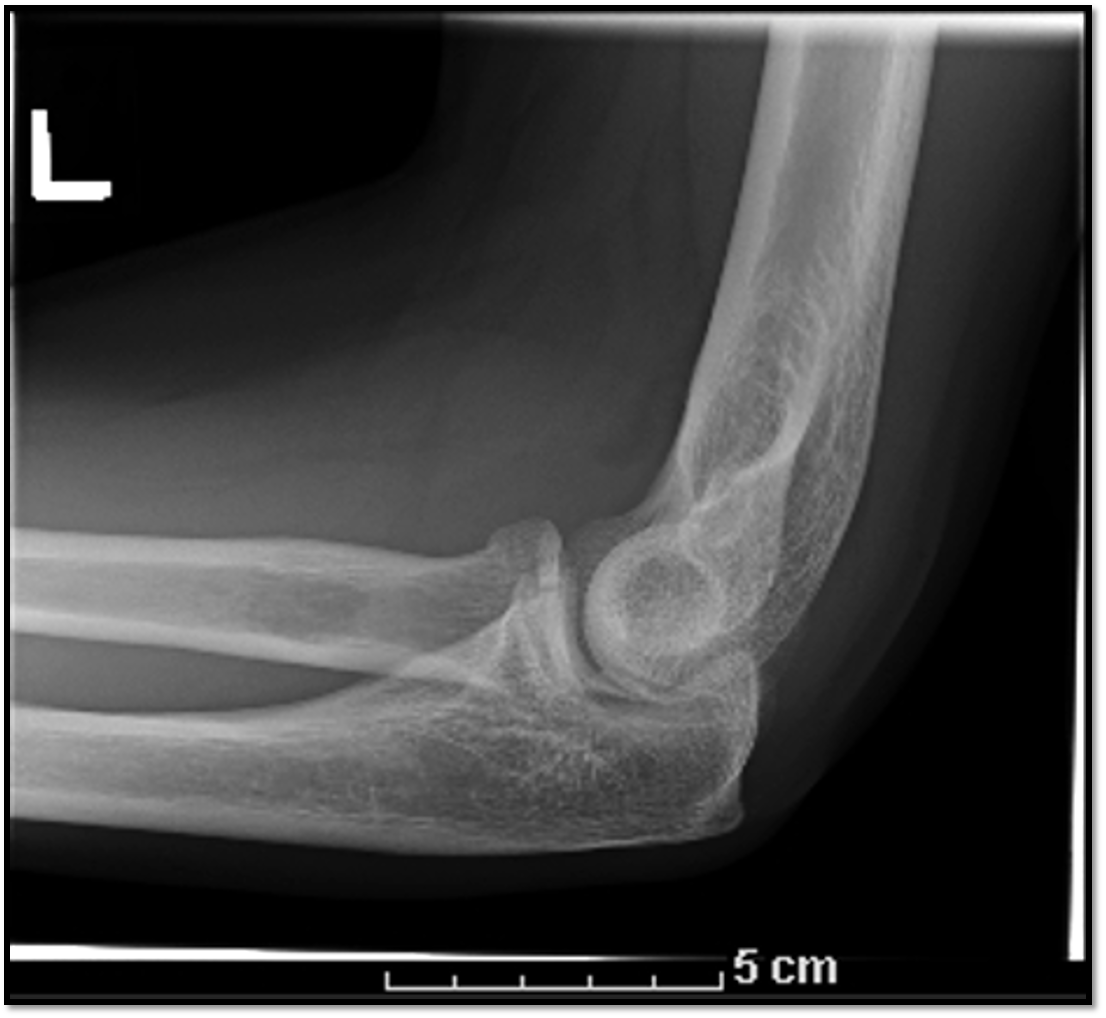

18

Lateral Elbow Criteria

A

• elbow flexed 90

• capitulum and trochlea superimposed

• articulating surfaces of the radial head and coronoid process are aligned

19

Q

What is the positioning fault?

How would you fix it?

• hand is too low

• lateral condyle more distal

• need to raise hand